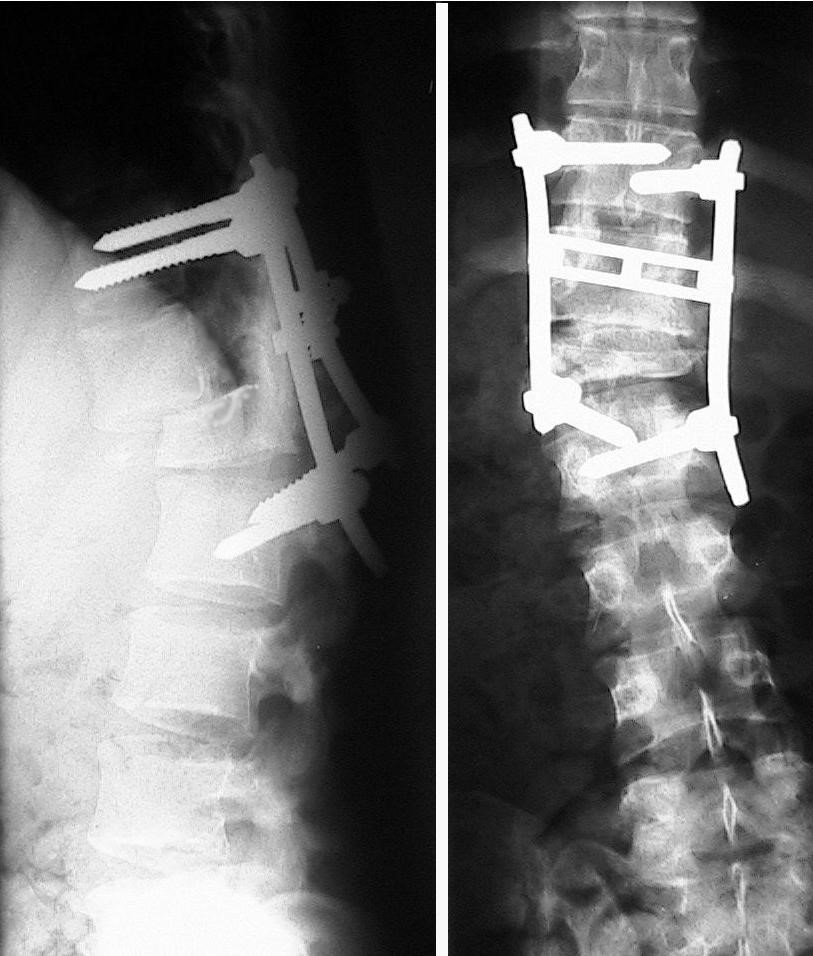

Do oddziału rehabilitacji przyjęto chorego lat 21 z rozpoznanym niedowładem kończyn dolnych bez zaburzeń w oddawaniu moczu po urazowym zwichnięciu kręgosłupa na poziomie Th12-L1 dwa tygodnie temu. Wykonano badanie przeglądowe kręgosłupa, które pokazane jest poniżej.

Pytanie 86